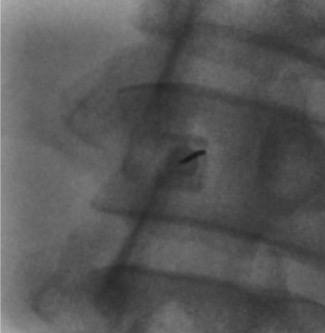

Fluoroscopic Views

When bedside US-guided or blind LP fails, fluoroscopy (prone or lateral decubitus) provides definitive guidance. The PA view confirms midline needle position; the prone oblique view opens the interspace and aligns the X-ray beam parallel to the disc for optimal interlaminar access.

- Advance spinal needle under fluoroscopic guidance: midline approach for straightforward cases; oblique or paramedian approach for significant degenerative disease or prior fusion